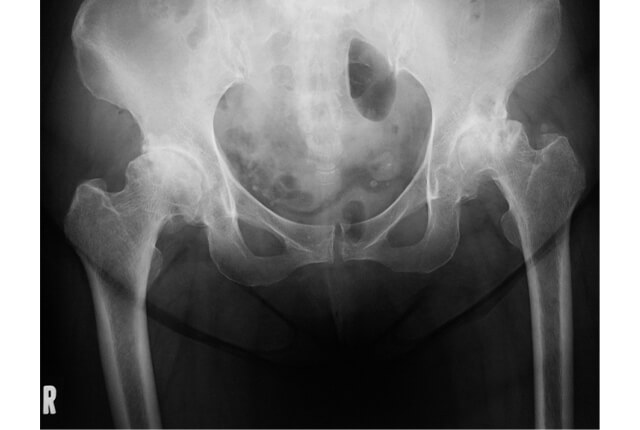

X線写真図3

診断はX線写真(図3)を用います。